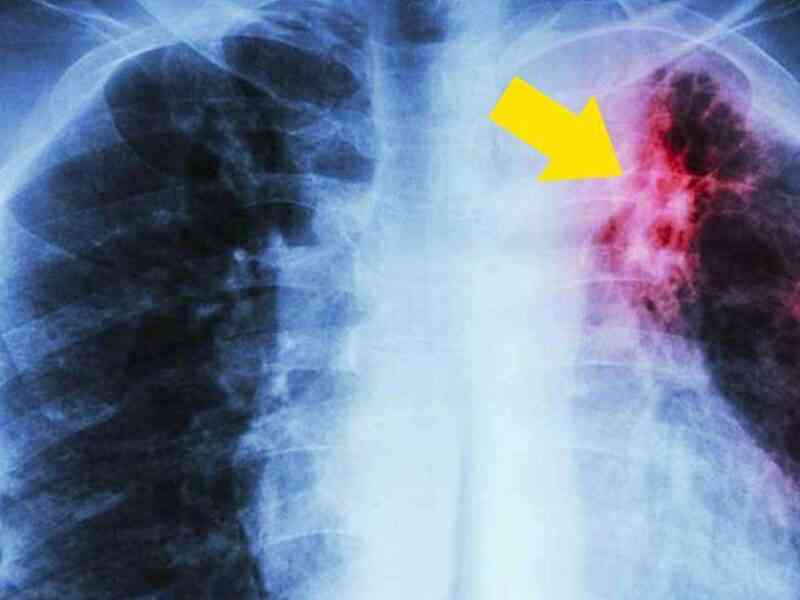

Fumar probablemente sea la acción que más muertes provoca en el mundo pero, a pesar de que sabemos las consecuencias, muchas personas lo siguen haciendo.

Hoy en día, muchos problemas de salud están relacionados con el tabaco, algunos de los cuales son enfermedades graves. Es cierto que cada…